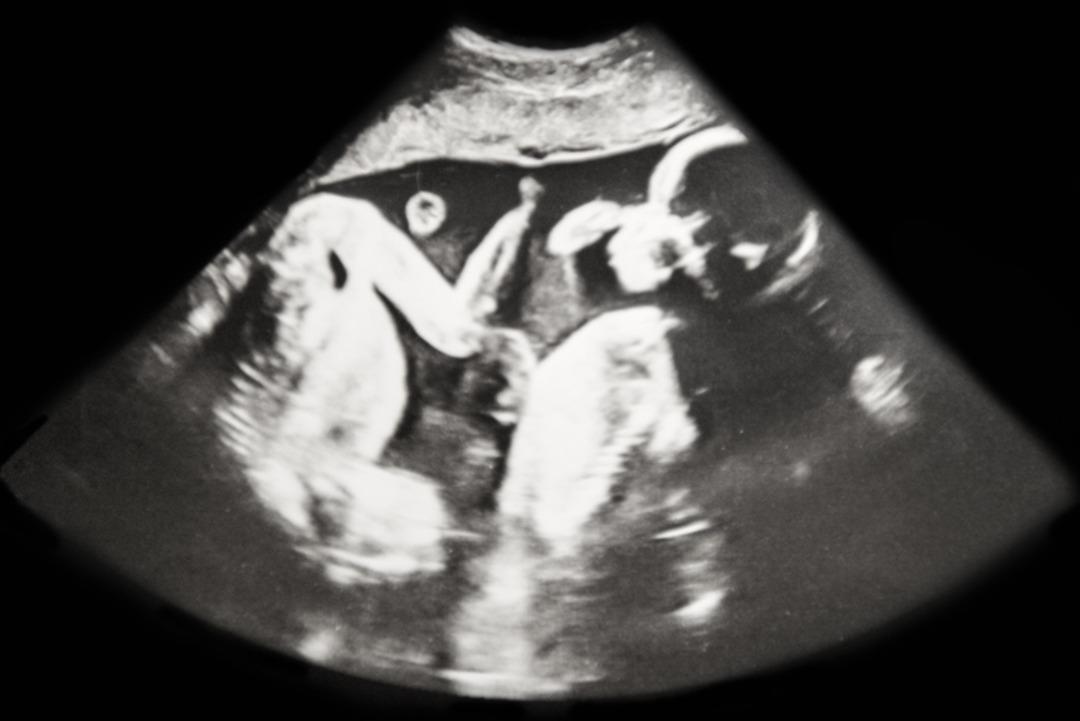

Tıp dünyasında ilk kez görülen bu vakada doktorlar, Ana Paula'nın kanındaki XY kromozomlarının, anne karnındayken ikiz erkek kardeşinden geçtiğini düşünüyor. Bu akılalmaz durum Ana Paula'nın 2022 yılında düşük yapmasının ardından yapılan araştırmalar sırasında ortaya çıktı.

Karyotip testi, Ana Paula'nın kanında XY kromozomlarının bulunduğunu gösterdi. Sonuçlar hem doktorları hem de Ana Paula'yı şaşkına çevirdi.

Yapılan DNA karşılaştırması, yalnızca kan hücrelerinin ikiz kardeşiyle aynı olduğunu ortaya koydu. Prof. Maciel, "Ağzındaki DNA'da, tenindeki DNA'da o kendisi. Ama kanında kardeşi var" diyerek durumu özetledi. Doktor Quaio, "Yani erkek kardeşinden bir parça içinde dolaşıyor" dedi.